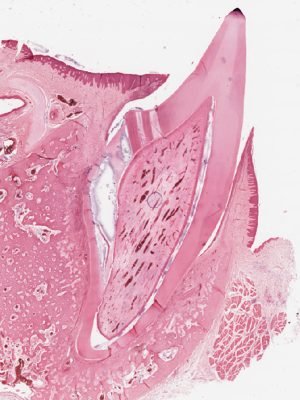

Tooth Eruption

Dentin

Pulp

Alveolar bone